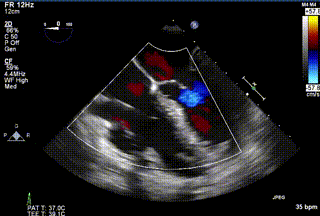

2021年12月24日,復(fù)旦大學(xué)附屬中山醫(yī)院葛均波院士團隊成功應(yīng)用LuX-Valve Plus為一例極重度三尖瓣反流(TR)合并房顫、房缺的患者完成了經(jīng)血管三尖瓣置換術(shù),這是在前基礎(chǔ)上,本周完成的第三例經(jīng)血管三尖瓣置換手術(shù),葛均波院士、周達(dá)新教授等與心外科魏來教授、賴顥教授,心超室的潘翠珍教授、李偉教授及麻醉科的郭克芳教授共同完成了本周手術(shù),均獲得圓滿成功!患者術(shù)后超聲顯示無TR,臨床癥狀明顯改善。本周手術(shù)的成功也為LuX-Valve Plus救治性臨床研究添上了濃墨重彩的一筆。

三例患者入院后,葛均波院士團隊周達(dá)新教授、潘文志教授、張源博士、陳莎莎博士及心超室的潘翠珍教授、李偉教授對患者的情況進行詳細(xì)評估和討論,最終決定為三例患者選擇LuX-Valve Plus40mm、50mm和50mm型號的瓣膜進行手術(shù)治療。手術(shù)后即刻拔除氣管插管,術(shù)后患者三尖瓣反流癥狀得到顯著改善,復(fù)查心超結(jié)果顯示人工三尖瓣瓣膜支架固定穩(wěn)定,瓣葉關(guān)閉形態(tài)未見異常,未見明顯反流。